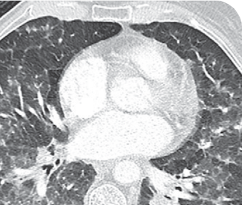

MRIa imagery of the brain. Green circles indicate baseline brain metastases.1

Response in primary and metastatic lesions1

SCAN 2: BRAIN

aMRI, magnetic resonance imaging.

MRIa imagery of the brain. Green voxels indicate decreased burden of metastatic disease; further quantified by accompanying measurement in green.1

SCAN 3: BRAIN

Pre- and post-treatment imaging, by Rosen EY et al, is licensed under Creative Commons License CC BY 4.0.

- Partial response to treatment that was confirmed at 2 months (34% tumor reduction)

- Grade 1 cough and Grade 2 fatigue

- Patient remains on VITRAKVI after more than 4 months of treatment

aBID, twice daily; NSCLC, non-small cell lung cancer; PR, partial response.